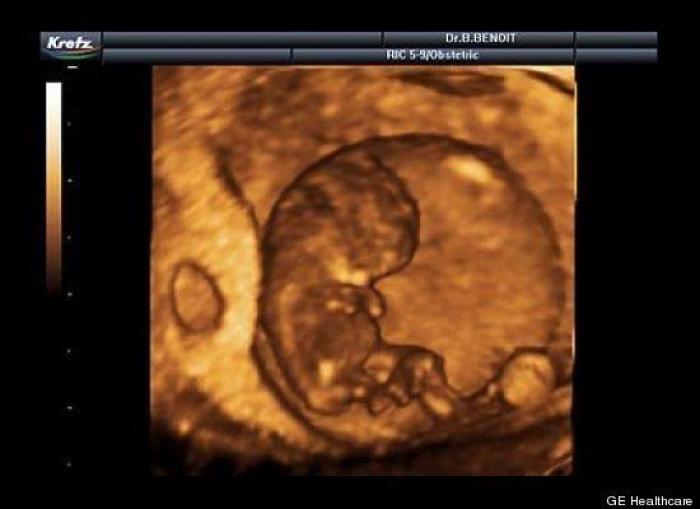

En esta galería puedes ver en fotos como es el desarrollo de un feto de semana en semana:

Desarrollo del feto, en fotos